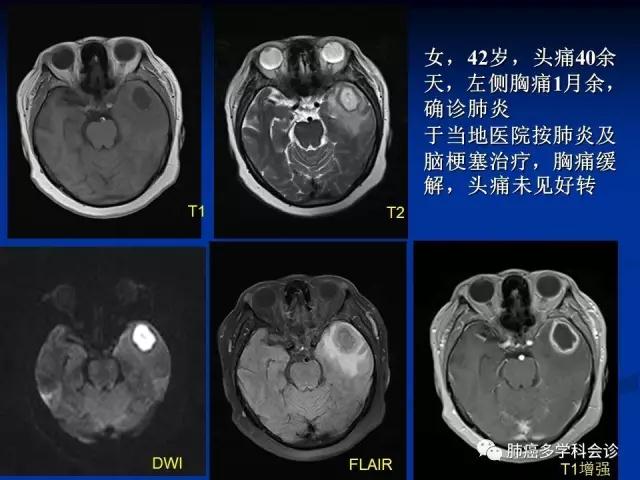

多数脑转移瘤的常规影像学表现具有一定的特征性,如“小病灶,大水肿”或呈脑内多发病灶

然而,在日常工作中常常会出现一些非典型表现的转移瘤,如单发的、不伴周围水肿的,部分脑转移患者可无明确原发肿瘤病史,对疾病的确切诊断带来困扰

弥散加权成像(diffusion weighted imaging,DWI)

常规MRI序列,主要包括T1、T2、FLAIR及增强Tl等,所显示的是病变的含水量和对比剂透过受损的血脑屏障进入病灶等情况

MRI弥散加权成像依靠不同组织间水分子弥散差异性造成的图像信号衰减来反映组织的结构特性

提供了与以往Tl、T2不同的新的成像对比,可反映病理状态下组织内水分子运动状态的异常改变

成为临床早期发现、有效鉴别病灶的重要辅助手段